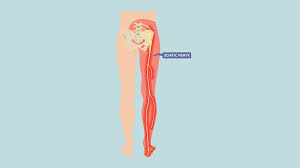

Download Sciatic nerve pain pictures